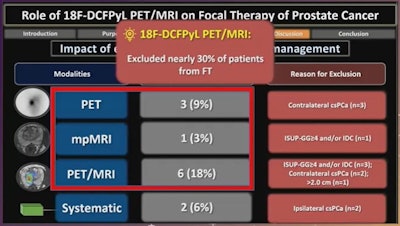

In a prospective trial, researchers at the University of Toronto sought to determine the role of Pylarify PET/MRI in the selection of patients with low or intermediate-risk prostate cancer for focal ablative therapy. They found the approach excluded nearly 30% of patients from the procedure, presenter Dr. Adriano Dias told attendees.

Ultimately, 22 patients were excluded from focal ablative therapy. PET detected contralateral clinically significant prostate cancer in 9% of patients, while mpMRI detected more advanced disease in 3%, and PET/MRI detected more advanced disease in 11% and contralateral prostate cancer in 6% of patients.

"Overall, F-18 DCFPyL PET/MRI (PET, mpMRI and PET/MRI) excluded nearly 30% of patients from focal therapy," Dias noted.